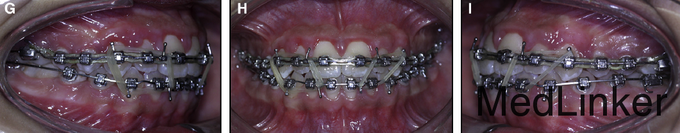

诊断:上牙弓严重横向不调。治疗:上颌颊侧骨皮质切开术+固定矫治+上颌腭侧固定扩弓。上颌上拖槽一周后行骨皮质切开术,如图,切开后全层翻瓣暴露骨皮质,于骨皮质上打孔,范围从牙槽骨顶端下方2mm到根尖下方2mm。根据牙槽厚度孔的深度从0.5mm到1.5mm不等,复位后间断缝合。同时腭侧粘接由带环,螺旋扩弓器制作的固定扩弓装置,即刻加力,转动完整的一圈。之后每周扩弓器打开1mm,连续8周,上颌牙弓被打开,扩弓器再维持2月,同时固定矫治器继续排齐整平。总疗程5个月2周。上颌宽度变化第一前磨牙间增加10mm,第二前磨牙间增加8.9mm,第一磨牙间增加8.3mm。但尖牙间宽度不变,这也是为什么扩弓后后期牙弓能够保持的原因,尖牙间宽度对维持牙弓稳定性非常重要。

3年后复诊,如图,仍然稳定。快扩和慢扩用于生长发育的患者,还是比较成功的,对于骨龄已经成熟的孩子,外科手术辅助的扩速腭部扩开可能是治疗的选择,本病例中的骨皮质切开术可以作为外科手术的替代方法,诱发颊侧的牵张成骨效应,促进表面骨质的沉积。相比于腭部切开手术,降低了风险。(该病例摘自Am J Orthod Dentofacial Orthop 2015;148:138-53 doi: 10.1016/j.ajodo.2014.08.023.)